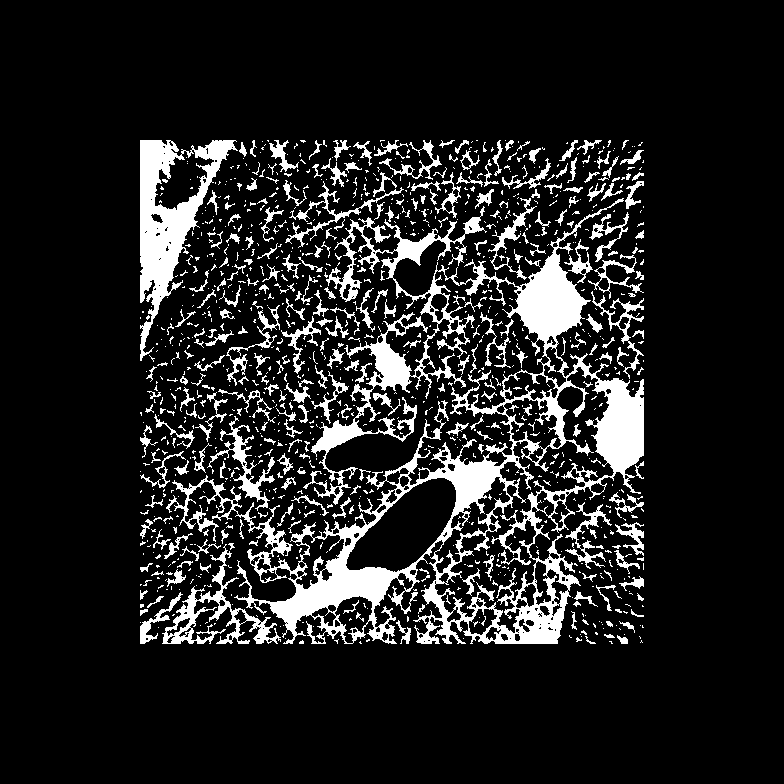

5 Benchmark procedure

To assess the performance of the HLSF, four phantoms with structural patterns of different complexity have been considered (Fig. 4). PH-1 in Fig. 4(a) is the segmentation of a reconstructed slice of mouse lung tissue at micrometer scale. PH-2 in Fig. 4(b) is a multilevel segmentation of a MRI scan of a human brain. PH-3 in Fig. 4(c) is a multilevel segmentation of a CT slice of a human lung. PH-4 is the well-known Shepp-Logan phantom [16].

Refer to caption

(a) PH-1

Figure 4: Set of simulated data used to benchmark the HLSF. PH-1 has 784 ×\times 784 pixels; PH-2 has 592 ×\times 592 pixels; PH-3 has 500 ×\times 500 pixels; PH-4 has 512 ×\times 512 pixels.